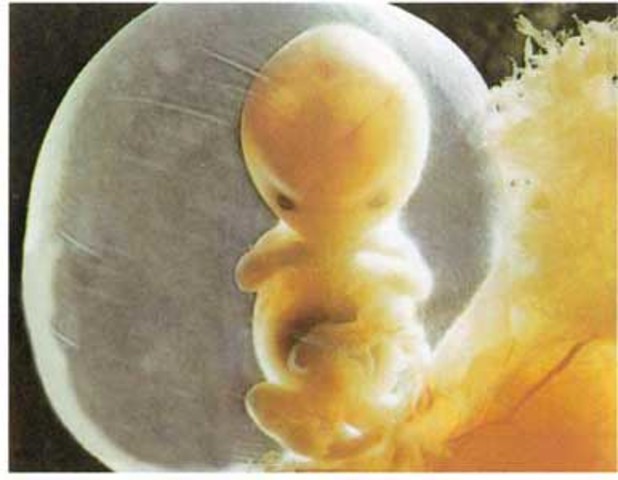

• Formacion de organos

Formacion de organos

El embrión se muestra en forma de C. La cabeza destaca a simple vista. Ojos y orejas comienzan a formarse. El corazón comienza a desarrollar sus válvulas y tabiques. Empieza la formación de órganos digestivos.

• Funciones vitales

Funciones vitales

Se cumple casi el mes desde la concepción. El embrión alcanza un tamaño de 6 milímetros. Comienzan a organizarse funciones vitales, tales como la respiración. Se forman la boca y la lengua. Aparecen unos pequeños estigmas que darán origen a las extremidades. Se forman las primeras células de la piel.

• Primer mes

Primer mes

Durante esta etapa, la cabeza y el cerebro se desarrollan rápidamente. Comienza la división cerebral de los dos hemisferios. El embrión alcanza un tamaño de 12 milímetros.